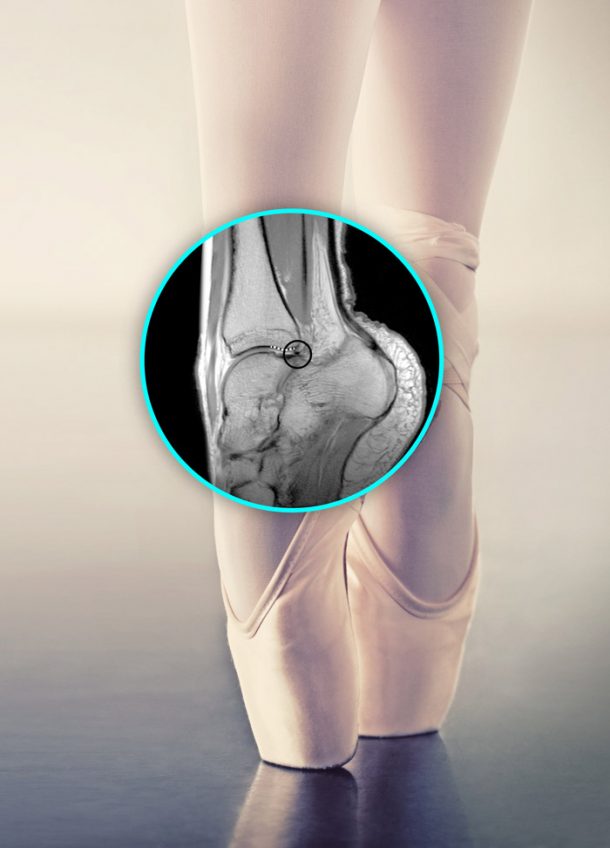

The ballet blog Stress Fracture understanding bone stress injury Do Ballerinas Have Foot Problems Treatment depends on the type of injury. Stress fractures in the metatarsals, sprained ankles, bruised toenails, and achilles tendon issues in the heel are common due to the repetitive impact and strain on the feet and ankles. Below are eight detailed strategies that can. Some common injuries from ballet include stress fractures, ingrown toenails, bunions, sprained ankles, and impingement syndrome.. Do Ballerinas Have Foot Problems.

Hypermobility A Common Foot and Ankle Problem in Ballerinas Do Ballerinas Have Foot Problems However, the demands placed on ballerinas’ feet and ankles can lead to various types of foot damage. Summary by experienced dancer with images. Over time, years of dancing jazz, tap, ballet and en pointe can result. The physical demands of dancing can lead to a wide range of foot problems and injuries. Treatment depends on the type of injury. Stress. Do Ballerinas Have Foot Problems.

Biomechanical Risks Associated with Foot and Ankle Injuries in Ballet Do Ballerinas Have Foot Problems How ballet affects the foot, avoiding injury and damage. Summary by experienced dancer with images. Treatment depends on the type of injury. Stress fractures in the metatarsals, sprained ankles, bruised toenails, and achilles tendon issues in the heel are common due to the repetitive impact and strain on the feet and ankles. Over time, years of dancing jazz, tap, ballet. Do Ballerinas Have Foot Problems.